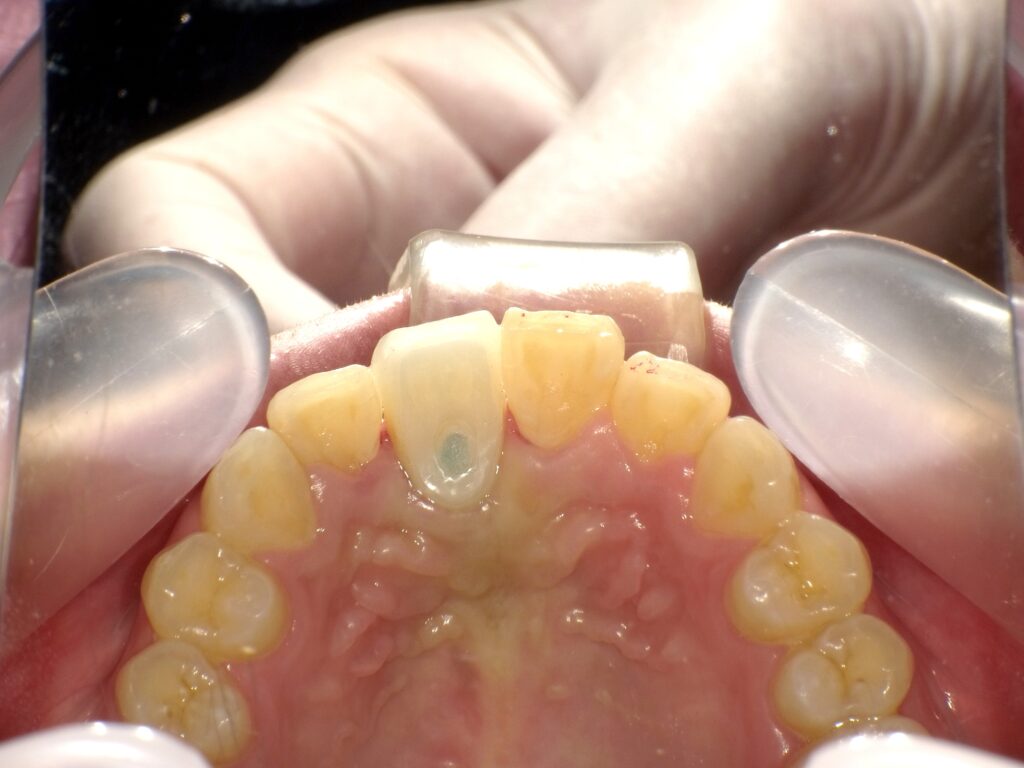

症例一覧 インプラント症例2 2024.11.25 治療内容インプラント主訴前歯事故で折れたのでインプラント治療を行いたい費用¥946,000(1本)治療期間7ヶ月 インプラント症例3 前の記事 インプラント症例1 次の記事